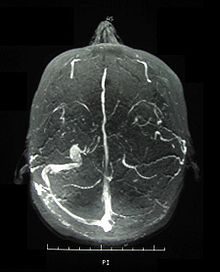

베체트병은 자반증만큼 많이 알려진 혈관염입니다. 베체트병의 정의는 동맥, 정맥을 포함한 모든 크기의 혈관에 침범한 혈관염입니다. 모든 크기의 혈관에 침범하기 때문에 증상도 그만큼 다양합니다.

경미하게는 구내염, 피부 결절, 외음부 궤양, 안과 병변부터, 심할 경우 신경계, 뇌, 장기 등에도 침범하여 생명을 위협하는 질환으로 발전하기도 합니다.

혈관은 우리 몸 머리끝부터 발끝, 오장육부까지 모든 곳에 분포된 기관입니다. 그렇기 때문에 혈관염이 생기면 증상도 그만큼 다양한 패턴으로 나타납니다.

혈관염은 증상의 변화도 빠릅니다. 증상이 쉽게 호전되기도 하지만, 반대의 경우도 많습니다. 적당한 치료시기를 놓치거나 잘못된 치료방법을 쓰면 중추신경계를 침범하기도 하는 것입니다. 그 결과 뇌졸중, 장출혈, 장천공처럼 생명을 위협하는 질환으로 빠르게 발전할 수도 있습니다.